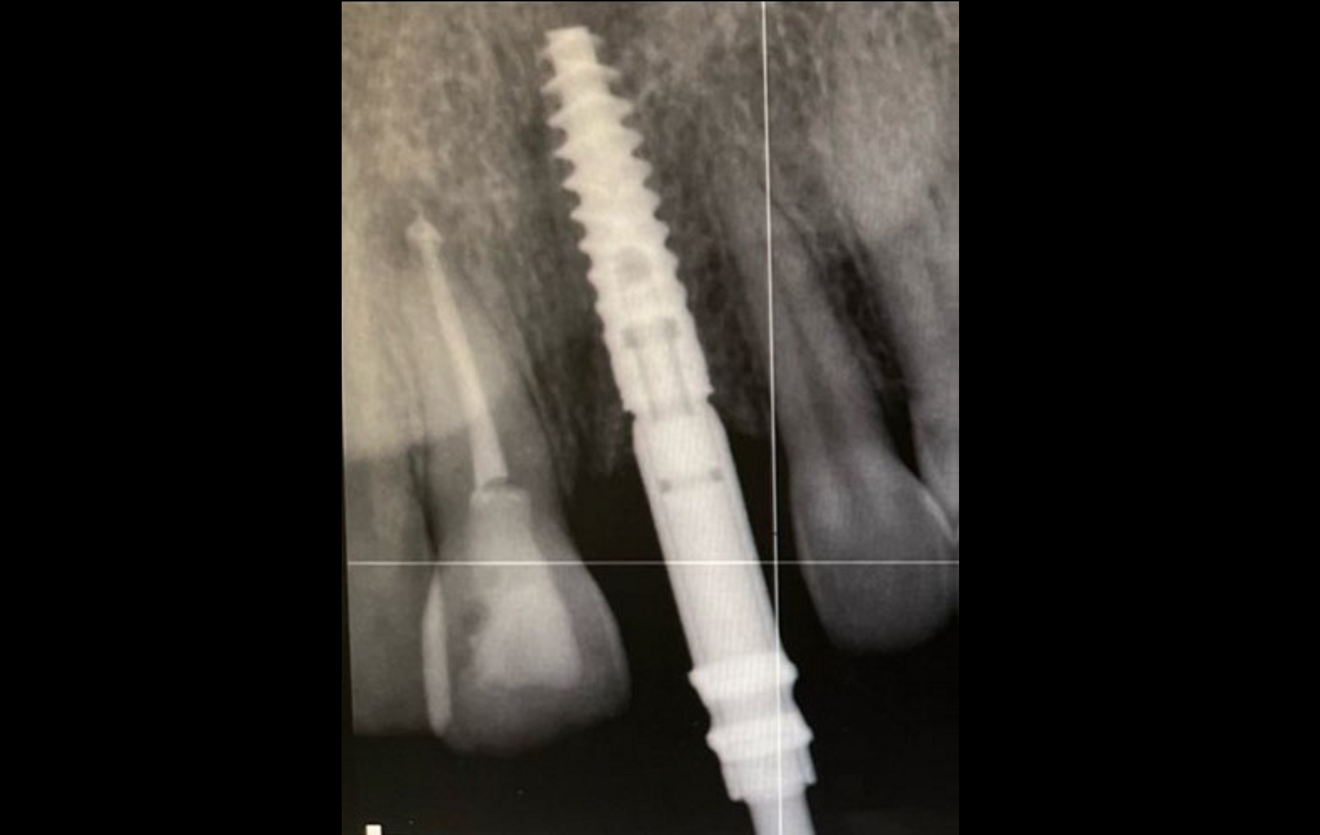

Figs. 2a–h: Demonstration of the study results through the case of a non-smoking 34-year-old female patient with a missing maxillary central incisor. Radiograph (a)...

...and clinical view at insertion of a narrow-platform 15 mm NobelActive implant (b).